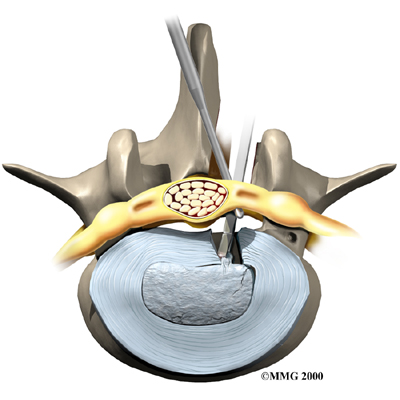

Microdiscectomy

Microdiscectomy is becoming the standard surgery for lumbar disc herniation. The procedure is used when a herniated disc is putting pressure on a nerve root. It involves carefully taking out part of the problem disc (discectomy). By performing the operation with a surgical microscope, the surgeon only needs to make a very small incision in the low back. Categorized as minimally invasive surgery, this surgery is thought to be less taxing on patients. Advocates also believe that this type of surgery is easier to perform, that it prevents scarring around the nerves and joints, and that it helps patients recover more quickly.

Related Document: FYZICAL Balcones Guide to Lumbar Discectomy